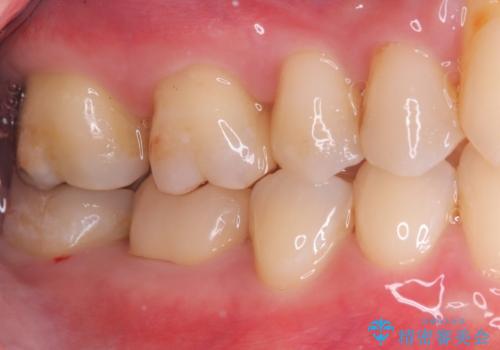

- 主訴:銀色の詰め物が取れてしまった。下の歯は笑うと見えるので、これを機に白くしたい。

保険適用のメタルインレーが脱離しており、歯冠色で審美性、適合性の良いセラミックインレーでのやり替えを提案しました。

メタルインレーが脱離した咬合面の窩洞内は、う蝕を除去し、セラミックインレーの厚みの担保とメタルタトゥー部分の除去を目的に形成を行いました。

インレーセット時はラバーダム防湿を行っています。